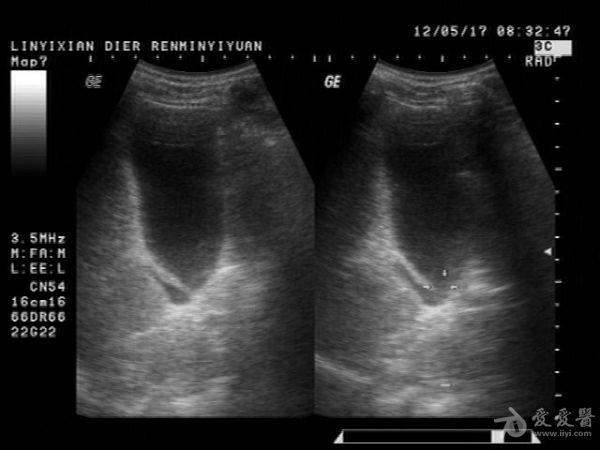

邹褶吧,不是憩室

很明显的胆囊皱褶,这种现象应该很常见的,肝硬化的时候胆囊比正常要大些

应该是胆囊皱褶。